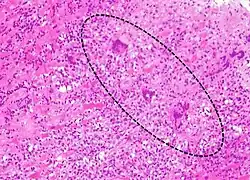

| A microscope image of myocarditis at autopsy in a person with acute onset of heart failure. The black dots are primarily lymphocytes infiltrating the myocardium. | |